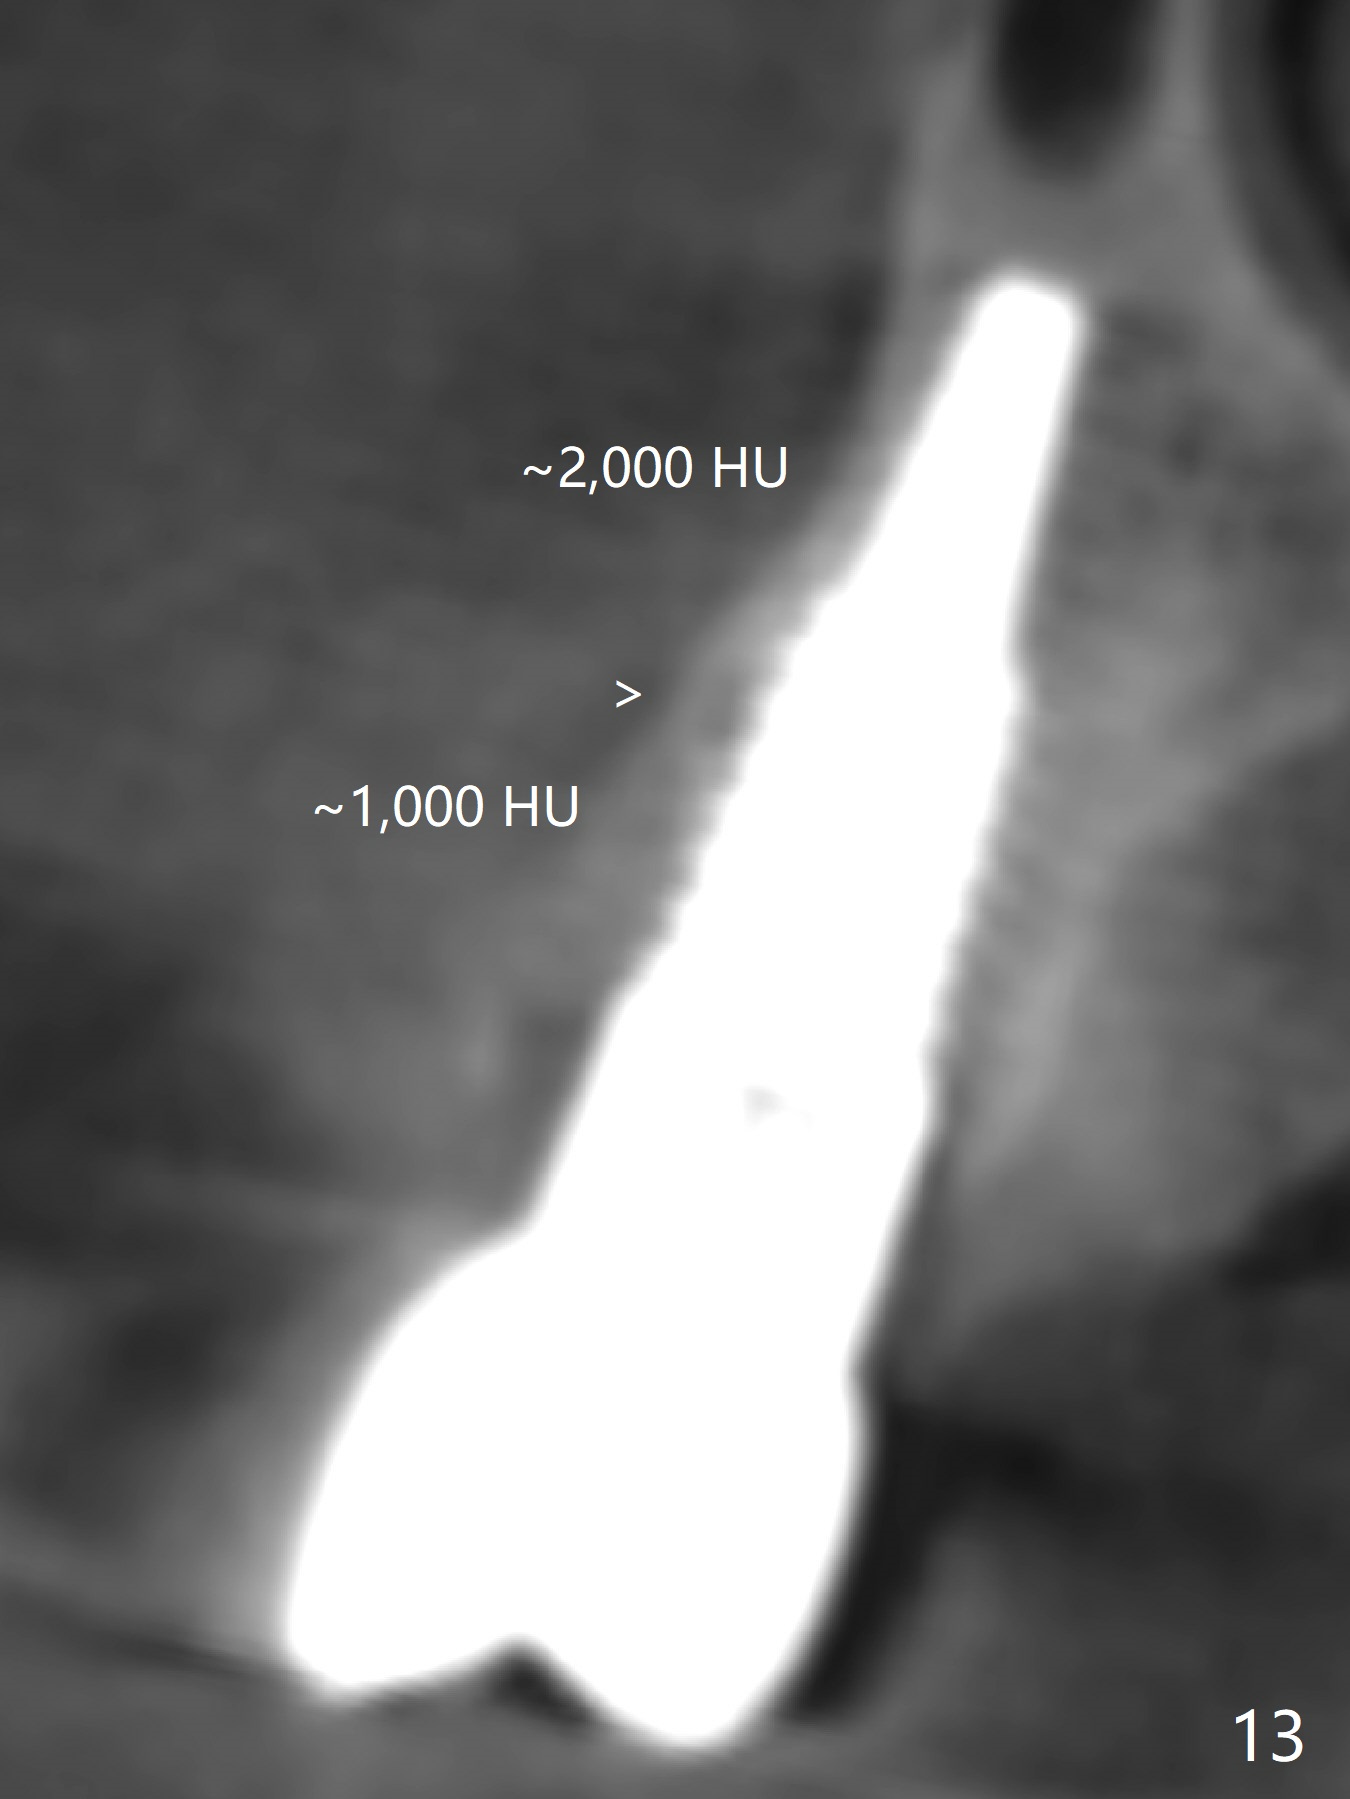

CT taken 4 years 9 months post cementation shows that the coronal portion of the buccal plate regenerates (Fig.12 between arrowheads, as compared to Fig.2,9). The density is ~1,000 Hounsfield Units, as compared to ~2,000 HU of the apical portion (Fig.13).